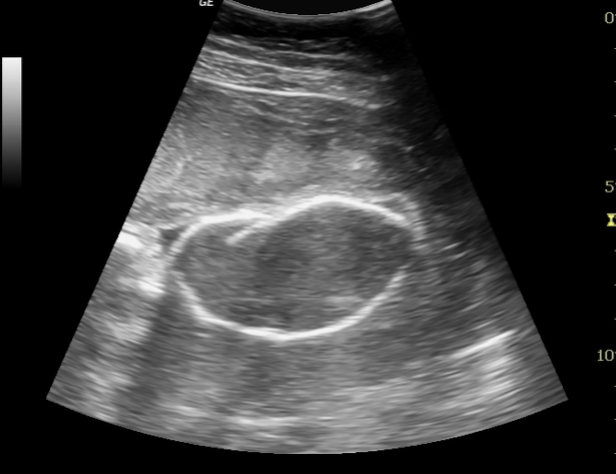

Fetal Demise U/S appearance:

may see skin, scalp, + generalized edema

spalding sign** (cranial bone overlapping)

ascites

oligohydramnios

abnormal position / spine curvature